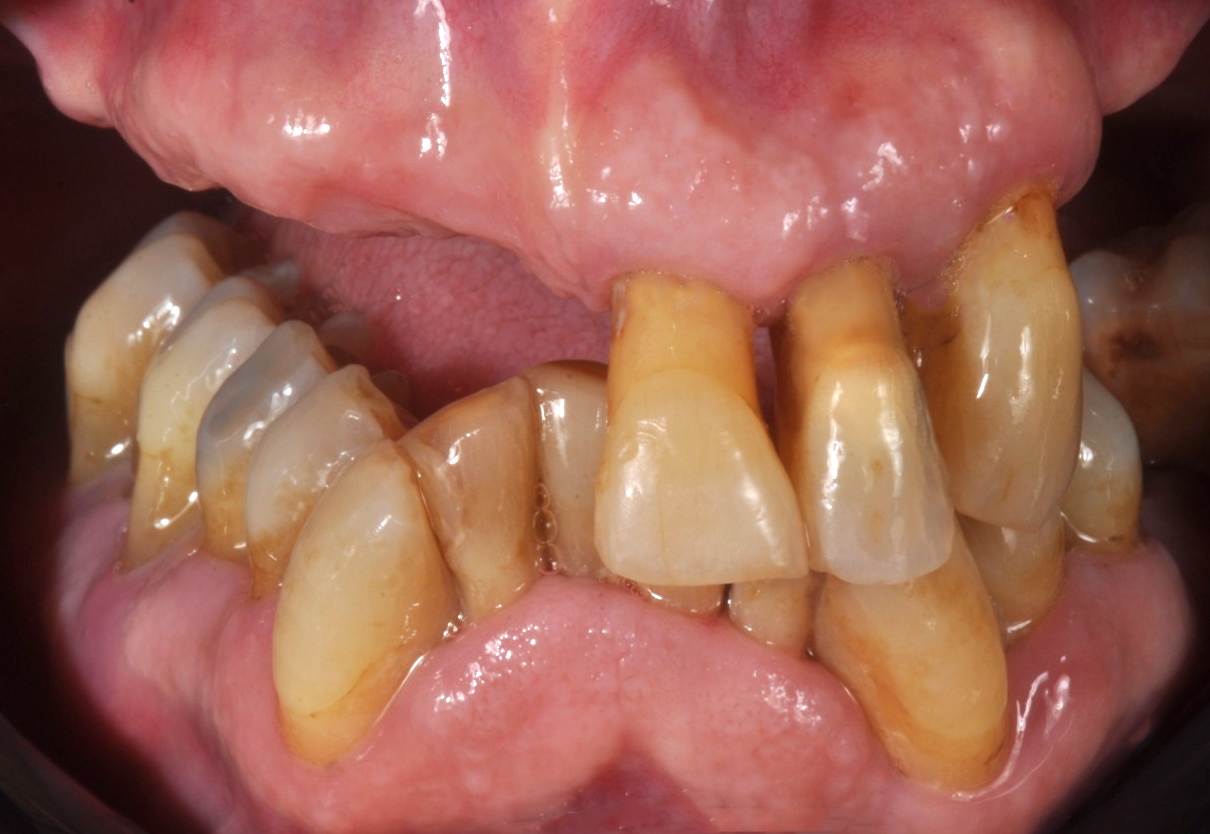

Il paziente era un uomo di Palermo, reso edentulo nell'arcata superiore dall'estrazione degli ultimi elementi dentari ormai irrecuperabilmente compromessi. Data l’età ancora non avanzata ed una vita sociale e lavorativa piena, chiedeva di essere riabilitato con un’arcata fissa e un'estetica eccellente.

La chirurgia, gestita con tecnica guidata, ha portato ad una prima protesizzazione provvisoria a carico immediato. Questo ci ha permesso di portare con tranquillità a maturazione i tessuti molli e l'integrazione degli impianti sottostanti (Fig. 2, 3, 4).

Fig. 2. Paziente prima dell’intervento implantologico